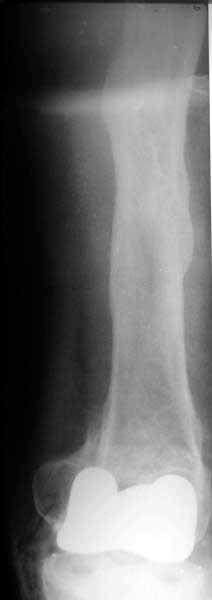

Well, finally i still performed antegrade nailing. After the distractor was applied, reduction of the recent fracture was obtained "automagically".

But the previous fracture resulted with some posterior displacment of the distal part, so antegrade nail would pass anteriorly, and retrograde nail, even a short one, would have penetrated anterior cortex proximally to the fracture. So perQ osteotomy was necessary to add some mobility at the level, and after that the nail was easily inserted to the distal fragment. The nail is solid, 13 mm, locking screws 6 mm. Locked statically.

The radiographs look excellent and a good outcome would be anticipated. The idea to osteotomize the femur shaft to compensate for the prior shaft malunion was clever and should work fine. I can't actually see the osteotomy on either radiograph. Is it more proximal than we see in these radiographsor so well aligned as to be not visible? Have you tried retrograde femoral nailing? Most people find it technically easier although not necessarily better than antegrade.